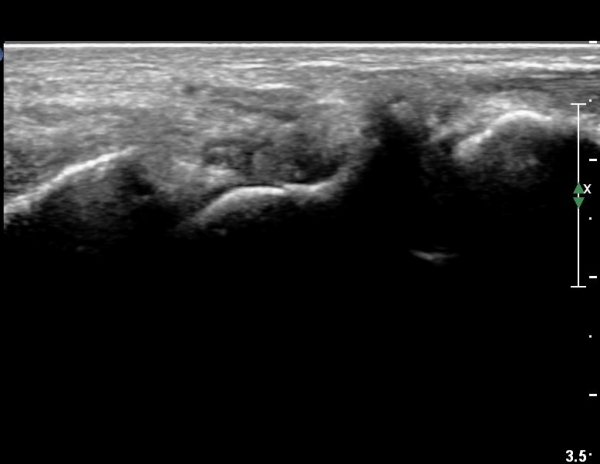

¼Õ¸ñ ¿ä°ñÃø ÁÖ»ó°ñ Á¾´Ü¸é °Ë»ç¿¡¼ ÁÖ»ó°ñ ÇÇÁú°ñ ¿¬¼Ó¼º ¼Ò½ÇÀÌ ¶Ñ·ÈÇÏ°í µ¿¹ÝµÈ ¿¬ºÎÁ¶Á÷ ºÎÁ¾ÀÌ °üÂûµÊ(»çÁø 3, 4)/

È®ÁøÀ» À§ÇÑ ÃÊÀ½ÆÄ°Ë»ç¿¡¼ ÁÖ»ó°ñ °ñÀý È®ÀÓ µÊ.